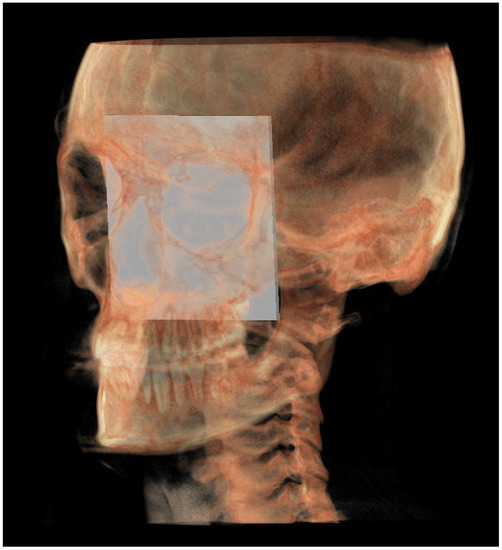

| SE neutral (SEn) | / | Point of a circumference with center in Ba and radius equal to MCFx, in which an angle of the skull base equal to 40.3° is obtained | / |

| Right SE neutral (rSEn) | / | Point taken arbitrarily on the right side of the SEn on the same arc of circumference | / |

| Left SE neutral (lSEn) | / | Point taken arbitrarily on the left side of the SEn on the same arc of circumference | / |

| Middle point MCF (MCFx) | / | Point of intersection between the plane on which the Ba lies and a line joining the left and right MCF | / |

| MCF neutral (MCFn) | Plane passing through the Ba, rSEn and lSEn which forms an angle of 40.3° with the PMn at the SEn point |

| PM neutral (PMn) | Plane parallel to the PM such as to form an ideal angle of 40.3° with the MCFn at the SEn point |

| Construction plane through Ba (CPBa) | Construction plane passing through Ba and parallel to the PM |